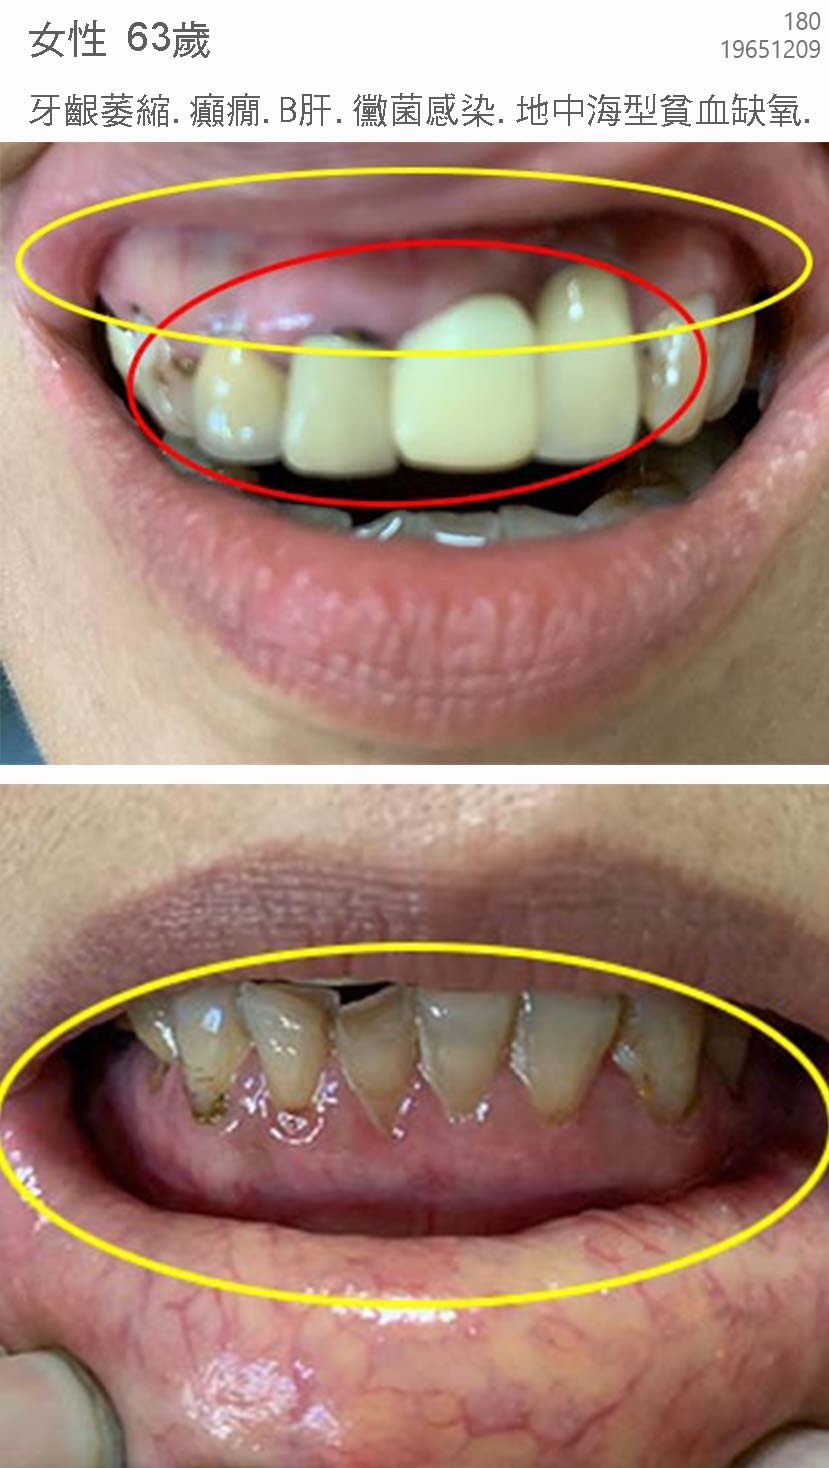

典型汞中毒症候群個案 hgscs0001